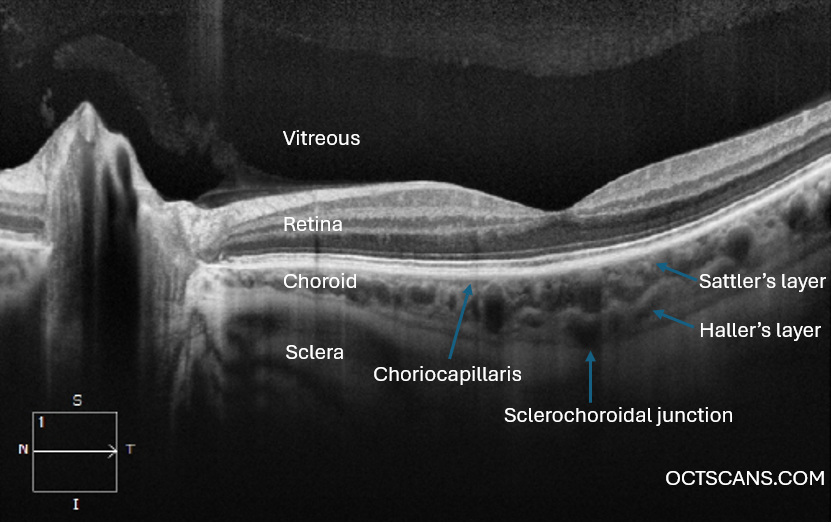

CHOROID

ANATOMY